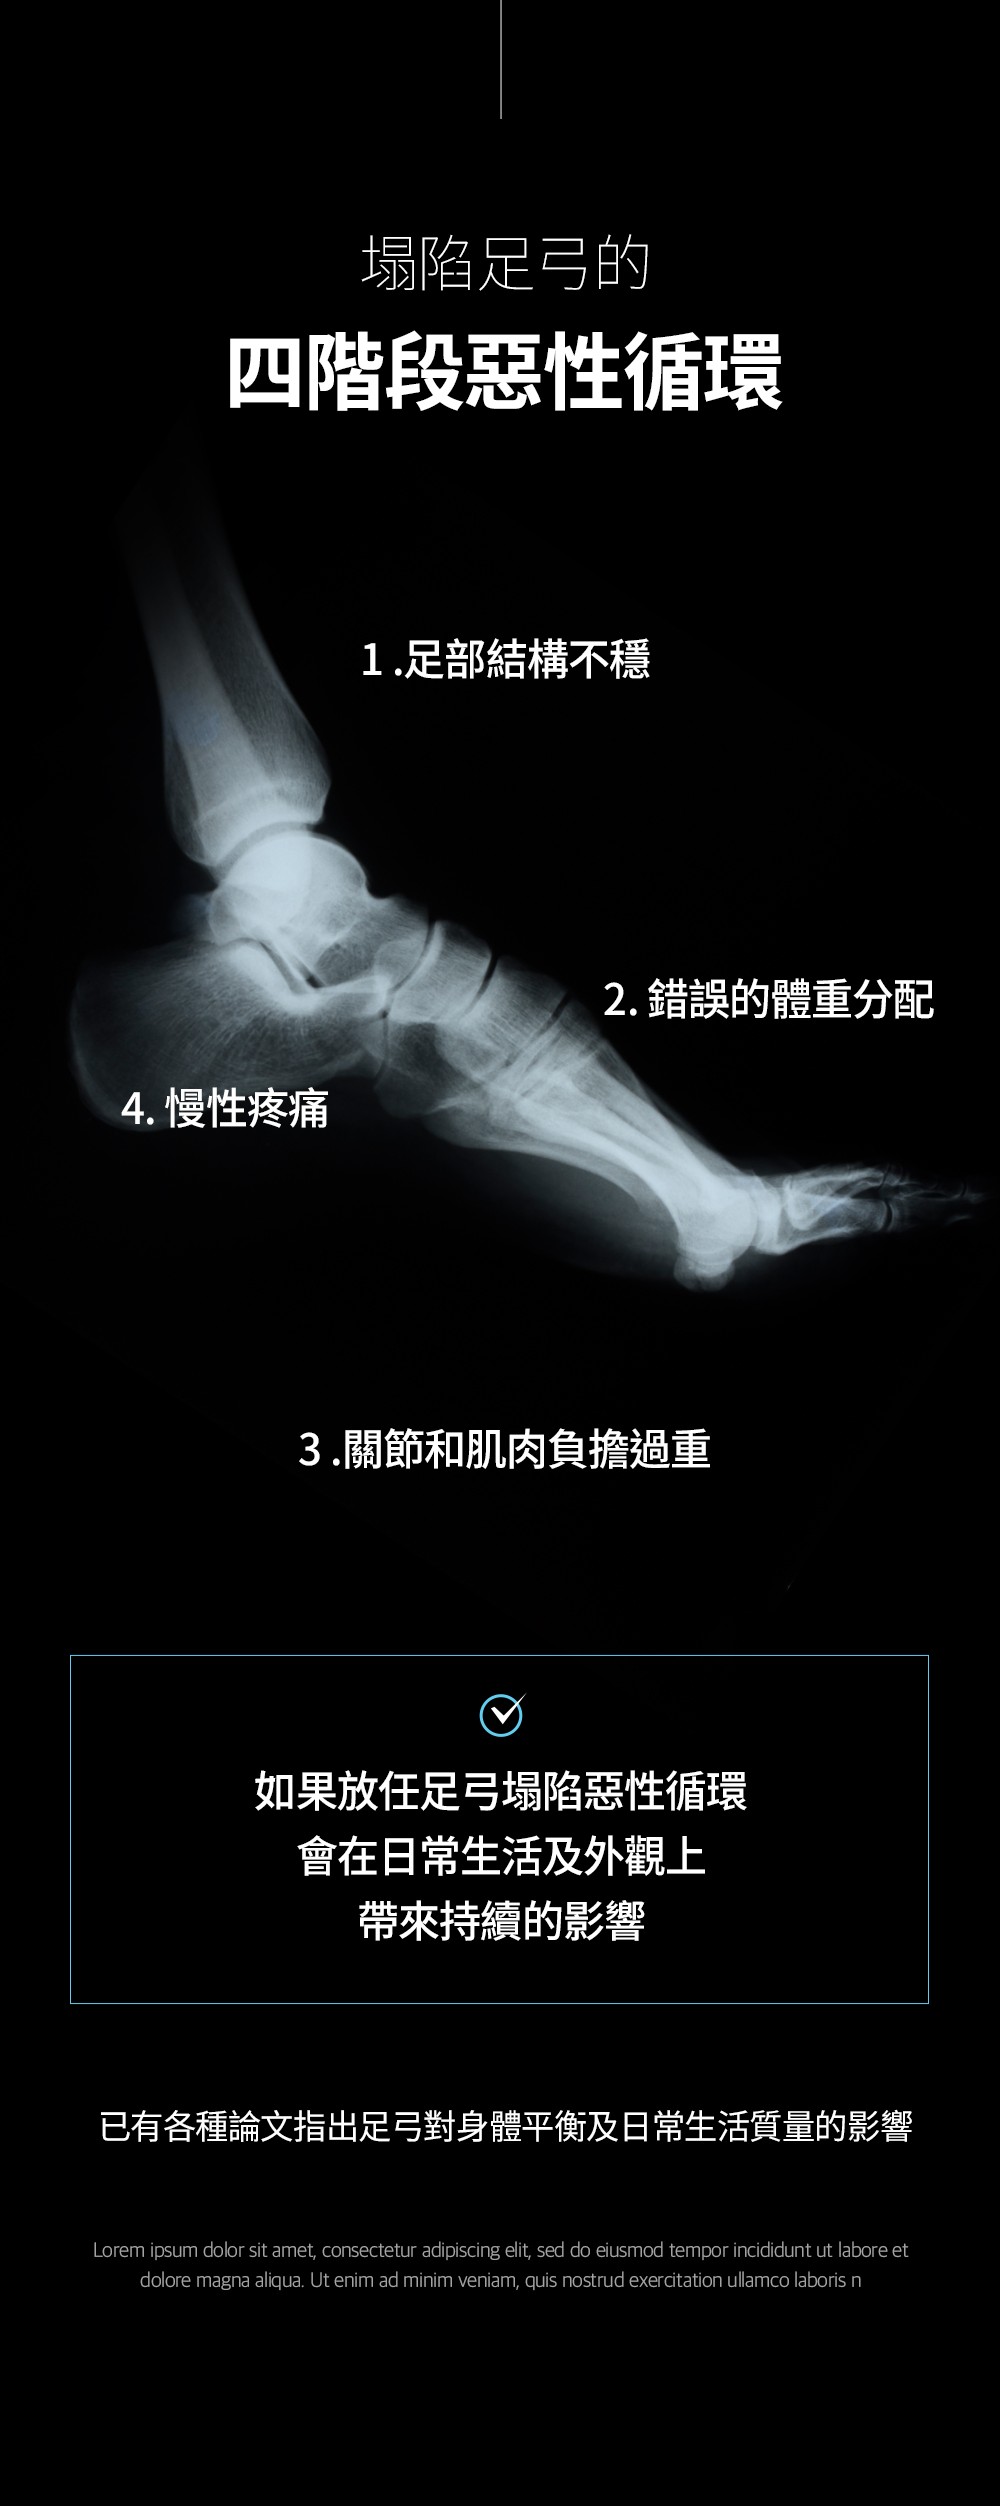

[足弓矯正] 人體工學設計的 ArchFit 🔬

✔ 支撐並矯正足弓 🦶

✔ 只需穿戴即可改善內八字、外八字及O型腿問題 🏃